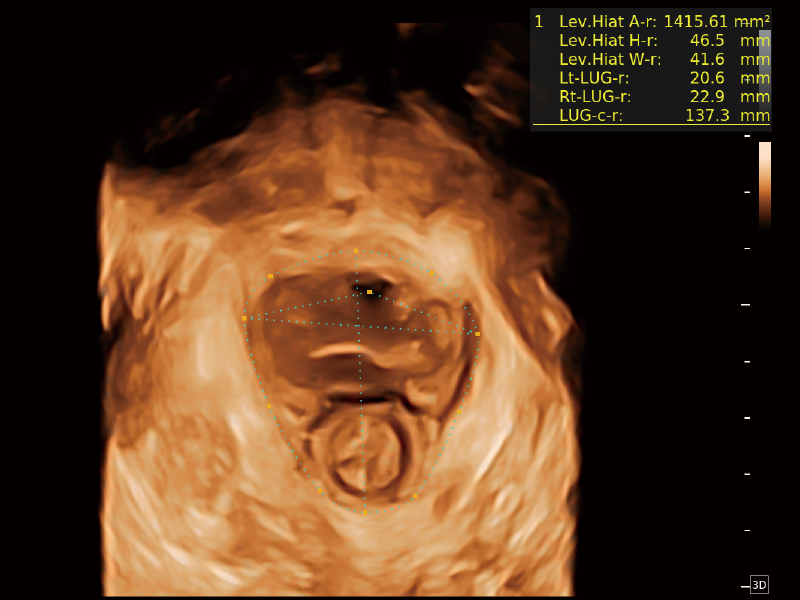

盆底自動(dòng)測(cè)量(2D)

盆底自動(dòng)測(cè)量(3D)